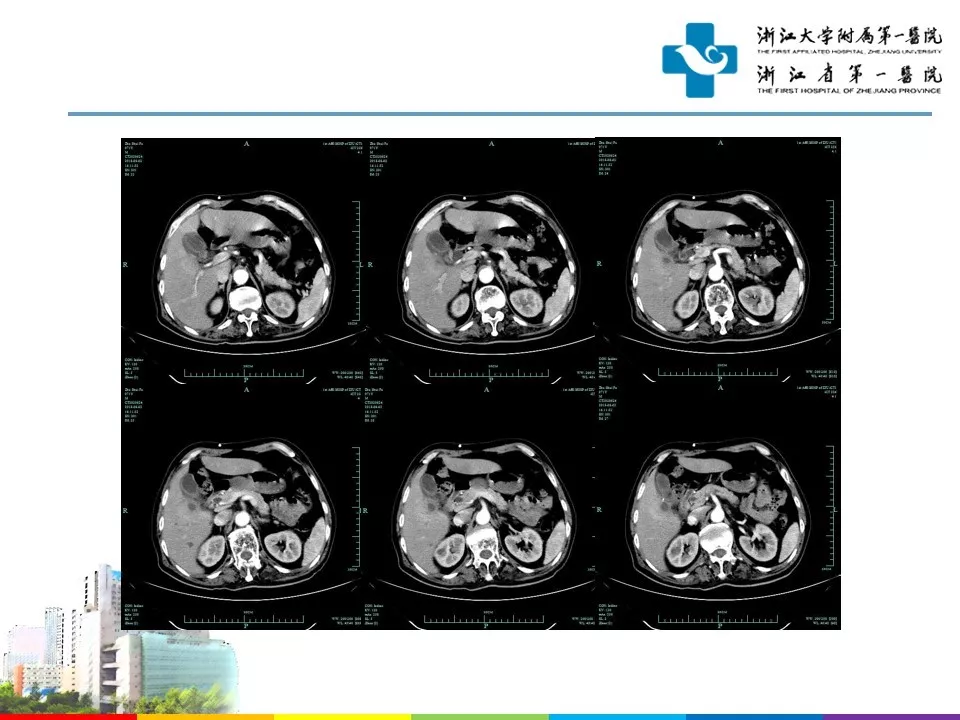

今天为大家分享的是《贝朗时间》第五十期,由浙江大学附属第一医院神经外科神经损伤与修复中心主任、急诊创伤中心主任杨小锋教授团队带来的:侧脑室-腹腔分流术后感染诊治,欢迎阅读、分享!